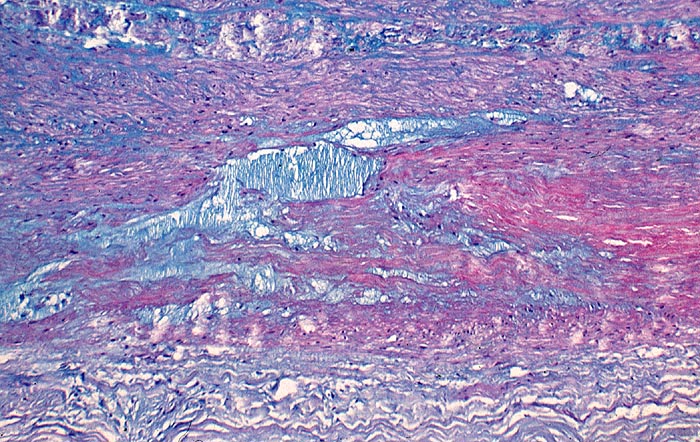

AP/ Zystische Mediadegeneration (Medianekrose)

Zystische Mediadegeneration (Medianekrose)

angeboren /genetisch/Missbildung

Kardiovaskuläres System

Aorta

Morphologie